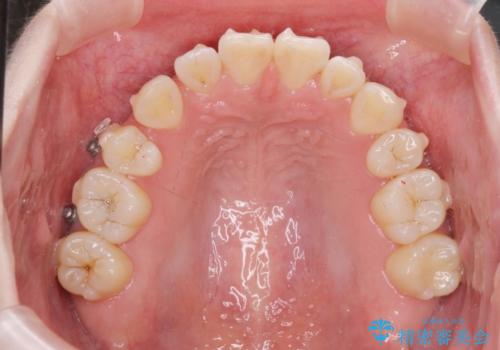

マウスピースで行う出っ歯の改善 後方移動

- 前歯の角度 奥歯の噛み合わせの改善をするために、矯正治療を希望され来院されました。

右側奥歯は上顎が相対的に前方に位置し(上顎前突)、そのため前歯の角度も突き出たようになり出っ歯のように見える状態でした。

マイクロインプラントを用いて、上顎奥歯を後方に移動させることで噛み合わせ・前歯の角度を改善していきます。